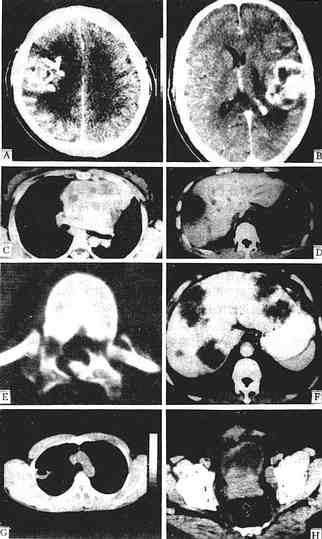

图1-2-6 CT图像

少支胶质细胞瘤增强,右额、顶叶有一较大不规则肿块,强化不均,周围有低密度水肿区

星形细胞瘤 增强,左额顶叶有一不均匀强化肿块,不规则,内有未有强化的低密度区,周围有低密度水肿区,中线结构右移

胸腺增生 平扫,胸腺区有一分叶状密度均一病灶,仍呈胸腺状,主动脉受压右移

肝脓肿 平扫,肝右叶有一低密度灶类圆形,中心部密度更低为脓腔,周边为脓肿壁呈“双边征”

腰椎骨折 平扫,椎弓多处中断,椎管变形,其内可见碎骨片

肝转移癌 增强,肝左、右叶多个大小不一、不规则低密度灶,周边有细的强化环围绕

肺脓肿 平扫,右上叶有一空洞性病灶,内壁光滑,并见气液平面,胸部X线片曾疑肺癌

前裂腺癌 平扫,前列腺分叶状增大,并向膀胱内突入